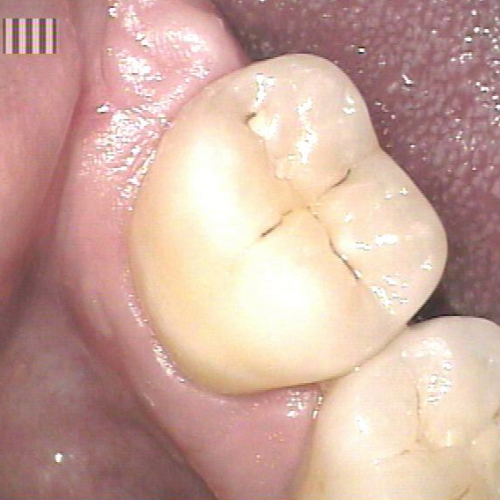

Ein Bild sagt mehr, als tausend Worte...

Um Ihnen Details in Ihrem Mund zu zeigen, die sich Ihrem Blick normalerweise entziehen, verwenden wir digitale Fototechnik in Form von hochwertigen digitalen Kameras, die extra für den Einsatz im Mund konstruiert wurden. Durch deren Einsatz erscheint das jeweilige Detail Ihrer Zähne formatfüllend auf einem Flatscreen-Monitor direkt am Behandlungsstuhl, so dass Sie ohne Probleme nachvollziehen können, auf was wir Sie hinweisen wollen. Auch erleichtert diese Technik bei Folgekontrolluntersuchungen die Entscheidung, ob sich eine zu beobachtende Auffälligkeit an einem Zahn über die Zeit negativ verändert hat.